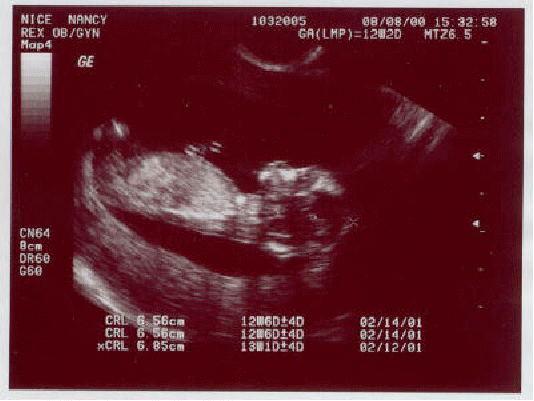

The machine displays the distances and intensities of the echoes on the screen, forming a two dimensional image like the one shown below of a foetus..

In a typical ultrasound, millions of pulses and echoes are sent and received each second. The probe can be moved along the surface of the body and angled to obtain various views.